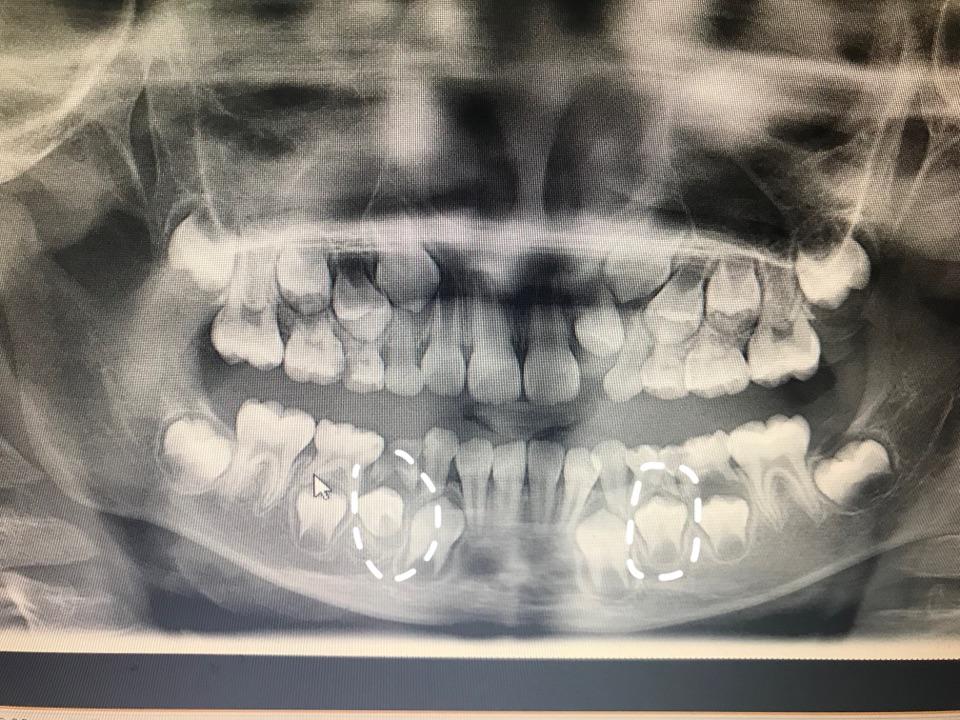

全景牙科 x 射线八岁儿童的问题不松动他的乳牙-持续乳牙

乳牙恒牙换牙期拍片情况

乳牙滞留拍片发现继承恒牙畸形中央尖一例